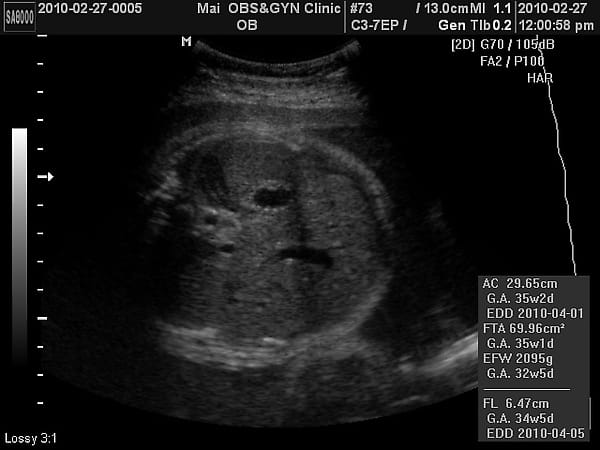

35W+1第八次產檢報告

已經照不到4d了,看看小老虎的大腿骨吧~   小老虎第八次產檢,驗尿ok,血壓偏,母親體重64.7KG。 小老虎上次產檢2050公克,這次2500公克,果然到了最後階段胎兒是以爆量在增長的。 血壓:83/50 心跳:101   產檢檢查乙型鏈球菌,自費400大洋。 《◎重要性:孕婦感染「乙型鏈球菌」的機率為10〜25%,若孕婦帶原,會在經陰道自然生產時傳染給新生兒,可能造成新 […]…